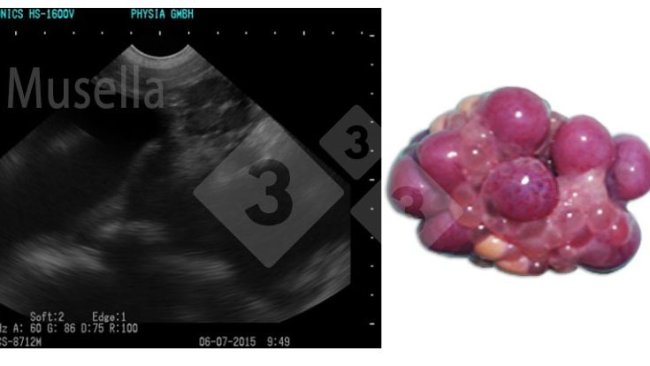

Here's how ultrasound can be used to visualize ovarian structures, assess the state of puberty, and diagnose ovarian pathologies.